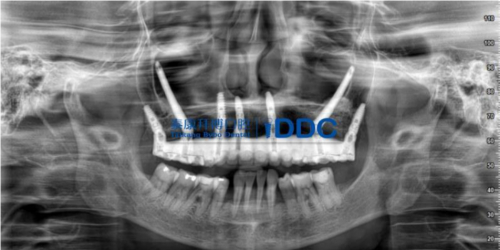

在上海泰康拜博口腔医院IDDC疑难种植中心,舒院长经过术前严谨科学的设计,结合现代口腔的国际先进种植技术和顶尖种植材料,为林先生成功进行了上颌双侧颧种植体种植(穿颧)手术,以及下颌即刻种植手术。

穿颧手术修复全景片

术后,林先生未出现明显术后反应,没有明显肿胀、疼痛等不适症状。当天就戴上了全口固定临时牙桥,即刻就可以正常进软食。